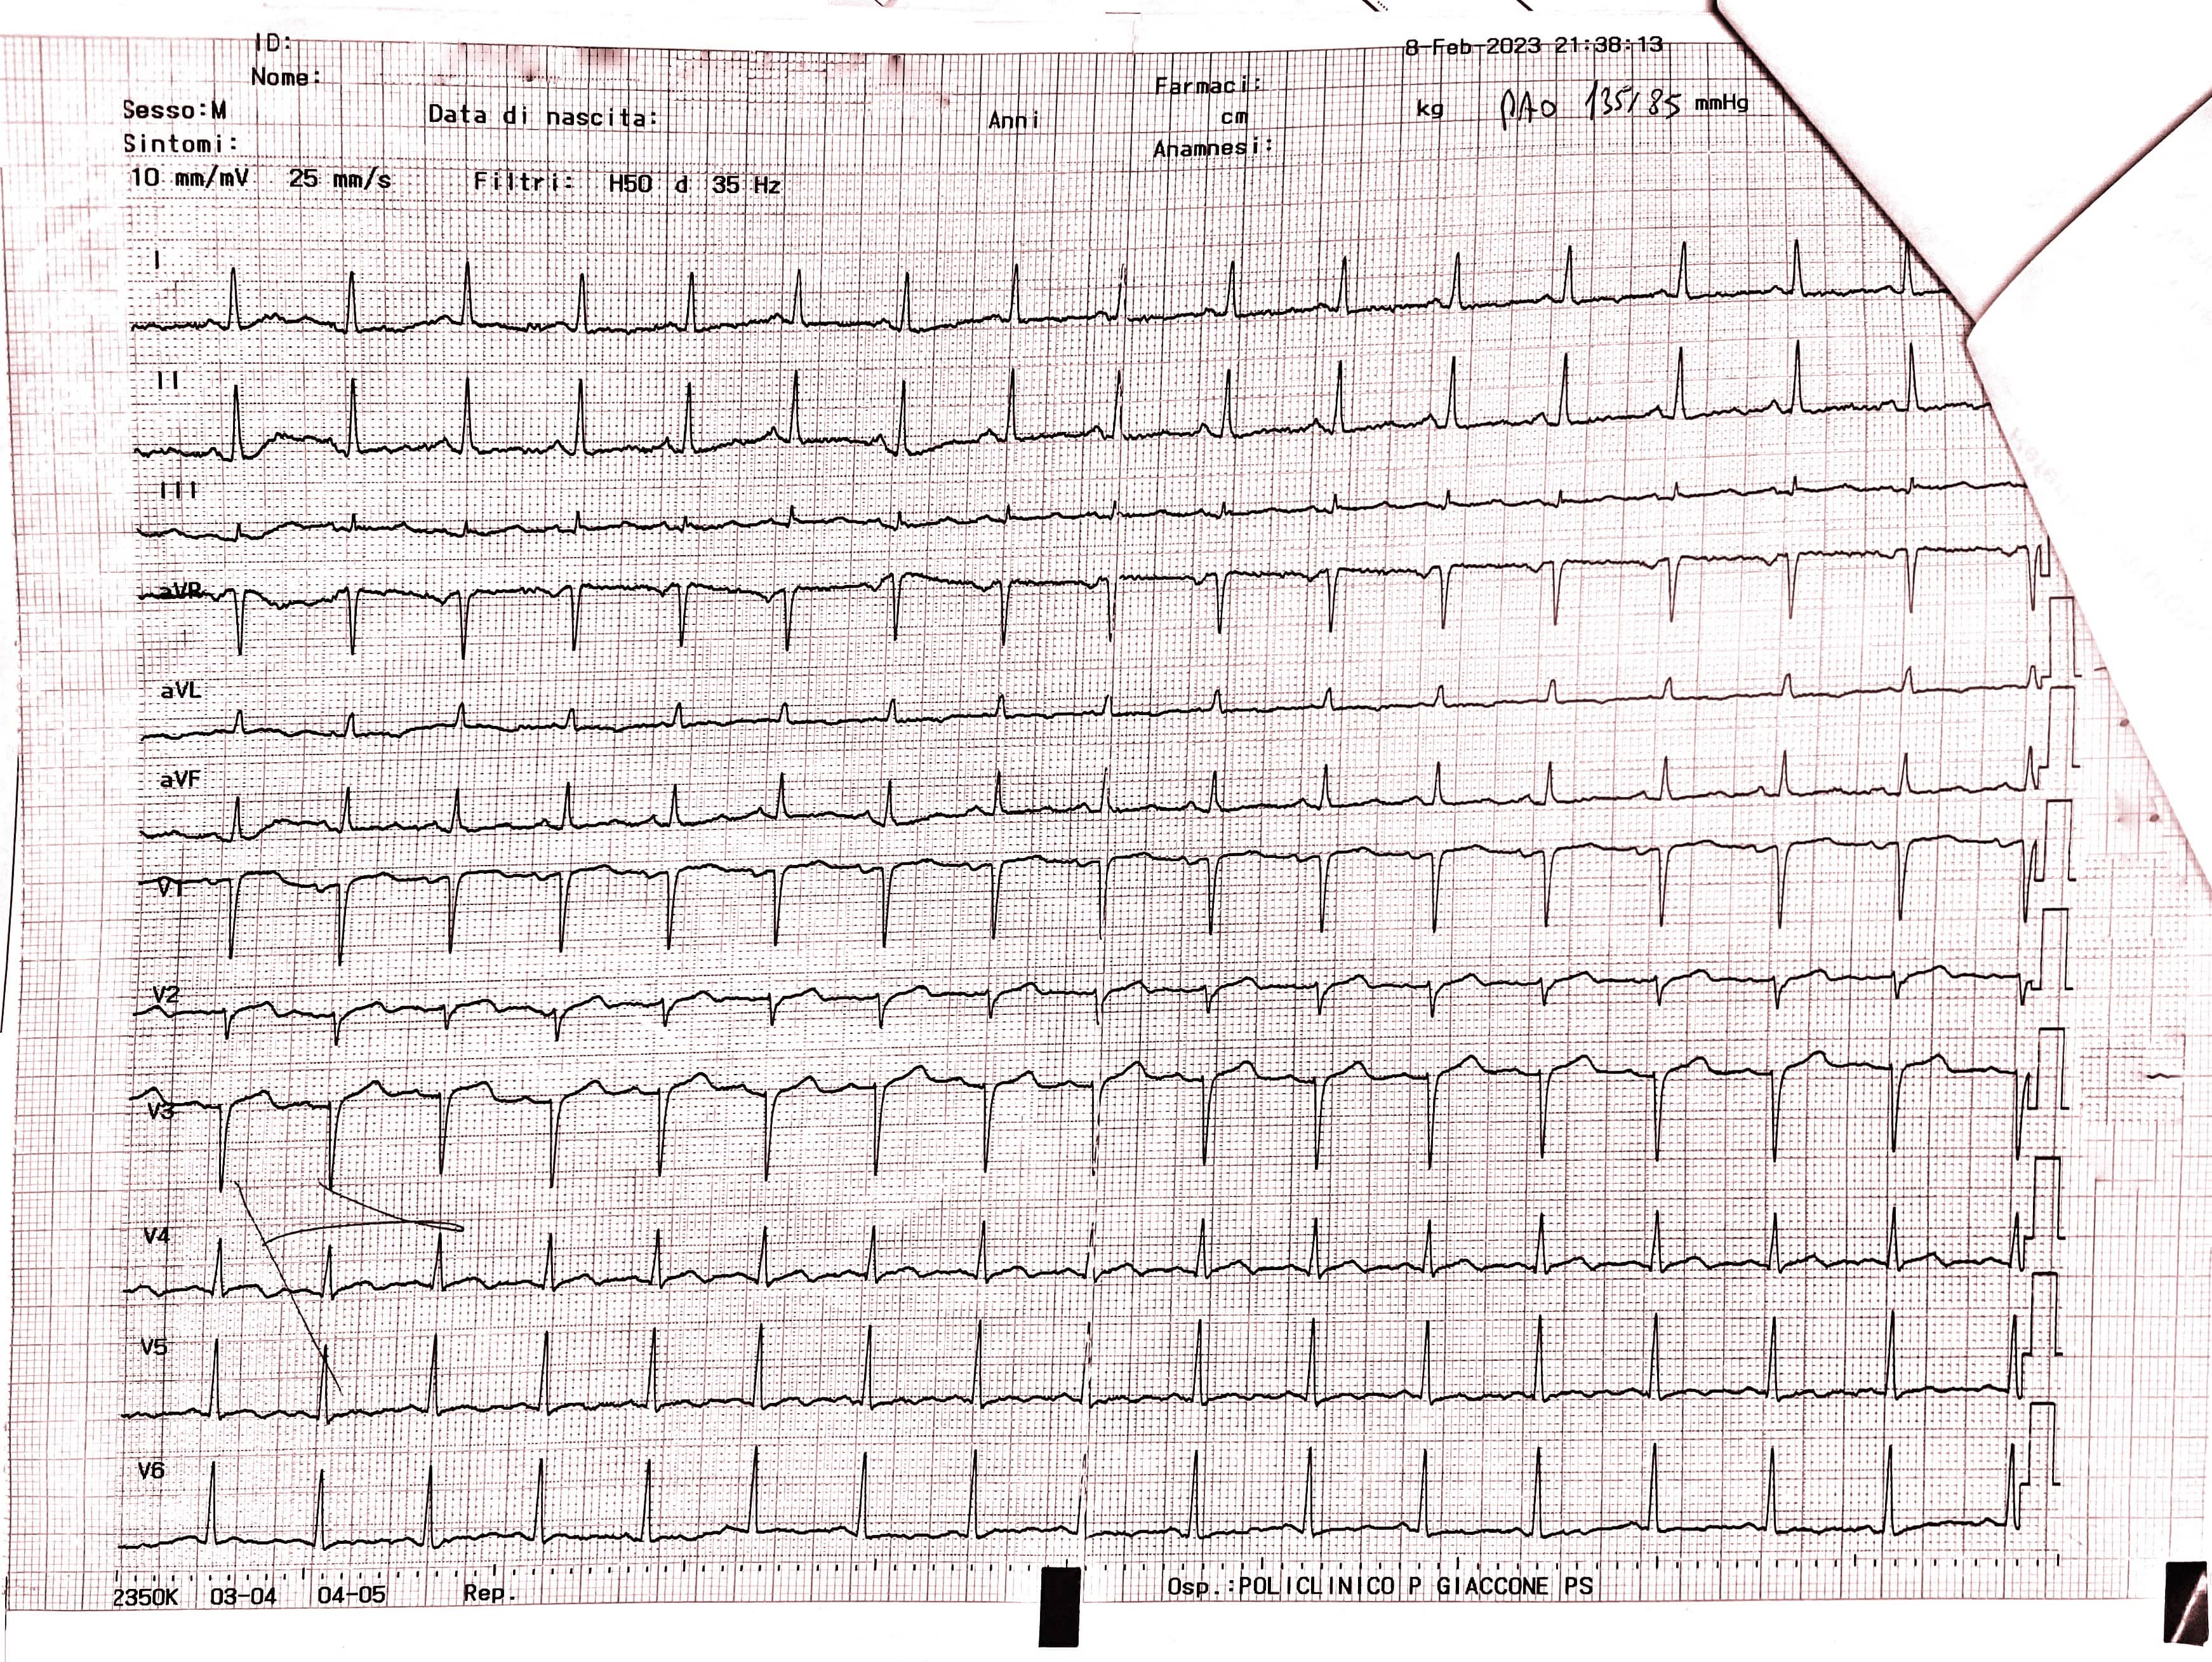

The ECG conducted in the emergency department (Fig. 2 — admission ECG) revealed sinus tachycardia with a heart rate of 103 beats per minute. Poor progression of the R wave in the precordial leads was observed along with minimal ST segment elevation from V1 to V3 in the context of widespread ventricular repolarization abnormalities.

Fig. 2.

Fig. 2.Admission ECG showing sinus tachycardia with a heart rate of 103 beats per minute. Poor progression of the R wave in the precordial leads was observed along with minimal ST segment elevation from V1 to V3 in the context of widespread ventricular repolarization abnormalities. ECG, electrocardiogram.

Upon admission, the patient’s blood pressure was 135/80 mmHg, with a heart rate of 71 bpm. The ECG displayed sinus rhythm, anteroseptal necrosis, negative T waves in leads DI, aVL, V4, V5, and V6, along with isodiphasic T waves in leads V2 and V3. Laboratory tests also revealed elevated levels of N-terminal pro-B-type natriuretic peptide (NT-proBNP) at 1949 ng/L, and low-density lipoprotein (LDL) at 114 mg/dL.